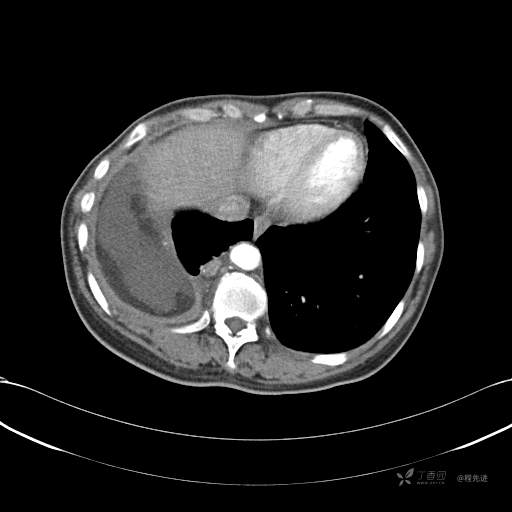

患者性别:女

患者年龄:51岁

简要病史:胸闷半年